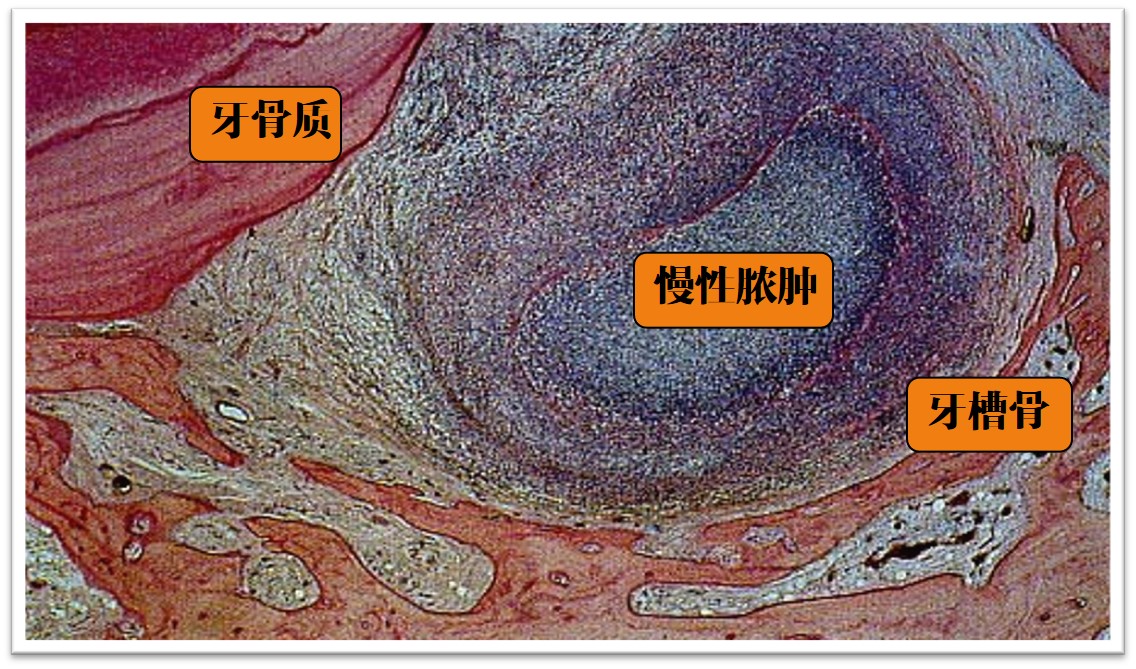

后 期:炎症范围逐渐扩大,根尖周组织结构破坏,代之以炎性肉芽组织,周围纤维组织增生(图9.2-2)。肉芽组织中可见泡沫细胞、含铁血黄素及胆固醇结晶。

图9.2-2 根尖周肉芽肿

2)病理变化(图9.2-5)

1. 根尖有脓性分泌物黏附,粗糙不平,根尖区牙周膜内脓肿形成。

2. 脓肿中央为液化坏死组织和脓细胞,周围为炎性肉芽组织,散在炎细胞浸润和新生毛细血管,外有纤维结缔组织包绕。

3. 根尖牙骨质和牙槽骨有不同程度吸收。

图9.2-5 根尖周脓肿